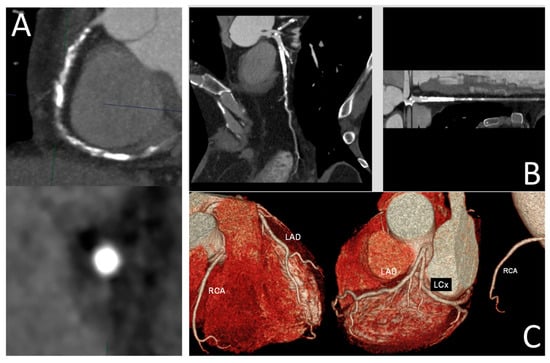

Advances in imaging technologies over the last few decades have revolutionized the role of cardiovascular imaging in the diagnosis and management of patients with cardiovascular disease. Traditional reliance on 2D and 3D imaging has been significantly augmented with the development of advanced technologies, including CT-derived fractional flow reserve (FFRCT), photon-counting CT, patient-specific 3D-printed models, virtual reality and mixed reality tools, and computational modelling, as well as the increasing use of artificial intelligence in cardiovascular disease diagnosis and risk stratification. The aim of this Special Issue is to collect submissions focusing on the use of the latest technologies in cardiovascular imaging. Research areas may include (but are not limited to) the following:

- 3D printing in cardiovascular disease;

- Virtual reality, augmented reality, and mixed reality in cardiovascular disease;

- Computational modelling in cardiovascular disease;